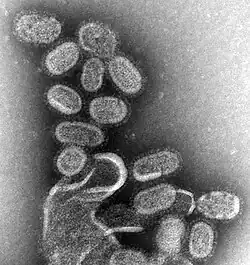

| Ampliação da estirpe de gripe A H1N1, responsável pela gripe espanhola em 1918 e pela gripe suína em 2009. | |